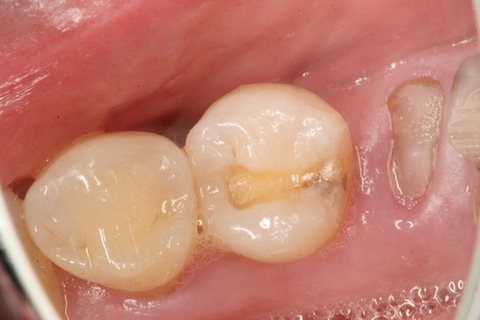

50代男性、右上5、6隣接面カリエス。冷水痛+。レントゲンで見ると、大きな虫歯に見えるが、肉眼ではそれほどでもない。エナメル質は全く溶けていないが、内部の象牙質だけが溶けている。この虫歯を見逃す歯医者はいないと思うが、なぜ象牙質だけが溶けるのか?という質問に答えられる歯医者は世界中探してもいない。できるのは僕だけwhttp://plaza.rakuten.co.jp/mabo400dc/diary/?PageId=11&ctgy=23歯はハイドロキシアパタイトというイオン電導性セラミックスが主成分で、電気(水素イオン)を通すことが知られていて、そのイオン化傾向を測ることもできる。http://plaza.rakuten.co.jp/mabo400dc/diary/201210150002/しかも象牙質の方がエナメル質よりわずかながらイオン化傾向が大きい。また、歯をpH3程度の酸性水溶液中に1ヶ月漬け込んでも溶けないが、外部から電圧をかけると簡単に溶ける。http://plaza.rakuten.co.jp/mabo400dc/diary/201210150000/これらのことから、この虫歯は象牙質とエナメル質を両電極とした局部電池が形成されることにより陰極となる象牙質だけが溶けると説明できる。ところが、世界中の歯医者はこのような虫歯を見慣れているが、なぜ、こういう虫歯ができるのかというのは知らない。ただ単に修復することができるだけだ。ところがCR充填すらできない歯医者は多い(というかほとんどだ)。なぜなら、世界中の歯医者は虫歯は細菌感染症だと思い込んでおり、虫歯を完全に除去しないと虫歯は再発すると信じ込んでいるからだ。このケースでは虫歯を完全に除去すると神経を取らざるを得なくなり、CR充填の適応症ではないと思い込んでいる。しかし、そうではない。虫歯を残しても、辺縁封鎖が完全なら、何の問題も生じない。要するに、虫歯があっても電気的に絶縁すればよいということだ。もちろん技術的な問題は大きいが。この症例のCR充填治療の所要時間は1時間。一回で終わり、神経も取らない、削って冠を被せるのも必要にならない。なんとコストパフォーマンスが高いことか!w